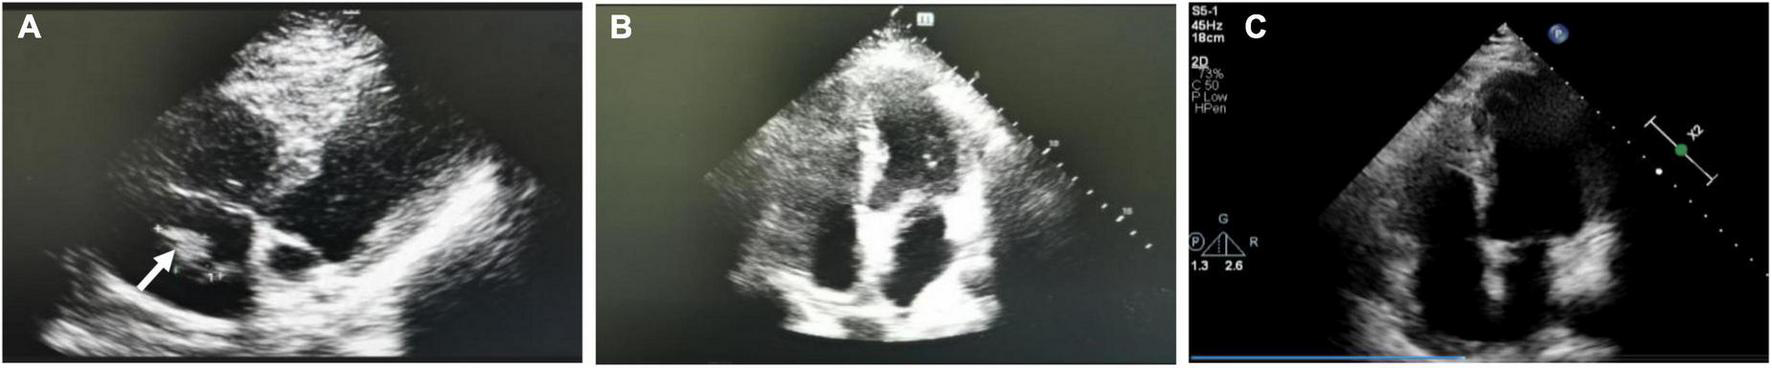

The patient was a 26-year-old male who presented to the Department of Cardiac Surgery with chest tightness and dyspnea. He had had a poor spirit, dyspneic appearance, heart rate 115/min, respiratory rate 30/min, blood pressure 106/92 mmHg and oxygen saturation 90%. Physical examination showed cyanosis, the breath sounds of both lungs were thick on auscultation, and a little phlegm rale could be heard. No obvious abnormality in other physical examinations. Laboratory test: D-dimer (0.9 mg/L), the chest CT showed some small pulmonary infarct areas in both lungs that were ignored by us until we made a correct diagnosis. The echocardiography found the right atrium mass (2021.06.21). It showed a long oval moderate echo mass in the right atrium with a length of about 5.29 cm and a less smooth surface, which seemed to be pedicled attached to the right atrioventricular orifice of the inferior vena cava (Figure 1A). The range of motion was large with the cardiac cycle, and the diastolic mass could be removed to the tricuspid orifice, and the systolic light mass returned to the right atrium. It is suggested that the solid space occupying in the right atrium, considering the right atrial myxoma, he was admitted to the Department of Cardiac Surgery. The pathological examination of the extract showed fibrinoid necrosis (Figure 1B), in which a small number of platelets and inflammatory exudates were seen, no obvious tumor cell components were found, and the total volume was 6 cm × 2 cm × 1.5 cm. Conventional anticoagulant therapy was given post-operatively. Ten days after surgery, the symptoms were significantly improved, no abnormal mass-like echo was detected in the cardiac cavity by echocardiography (Figure 1C). The patient was discharged from the hospital with warfarin (INR 2-3). However, less than a month after surgery, the patient came to the Department of Cardiac Surgery again due to dyspnea. The right atrial mass was revisited (3.41 cm × 0.81 cm, Figure 1D).

FIGURE 1

Images of first hospitalization and recurrence of right atrial mass. (A) The first echocardiography revealed a right atrial mass. (B) Pathological image of right atrial mass: a small number of platelets and inflammatory exudates. (C) Echocardiography at 10 days after operation showed that the right atrial mass disappeared. (D) Right atrial mass revisited (Less than one month after surgery) White arrows represent thrombus.